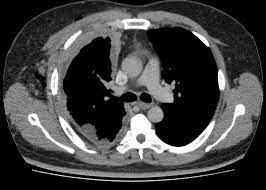

Carcinoma de células renales. Revisión

El carcinoma de células renales (CCR) es una neoplasia maligna frecuente que a menudo se diagnostica de manera incidental en un estudio de imágenes abdominales. El setenta por ciento de los pacientes son diagnosticados con CCR en estadio I y el 11% de los pacientes con estadio IV. Los tratamientos de primera línea para el CCR en estadio temprano son la nefrectomía parcial o radical, que puede resultar en una supervivencia específica para el cáncer a 5 años de más del 94%, las técnicas ablativas o la vigilancia activa. Las nuevas opciones de tratamiento para pacientes con CCR metastásico incluyen inhibidores de puntos de control inmunitarios e inhibidores de la tirosina quinasa. JAMA.   28 de agosto de 2024